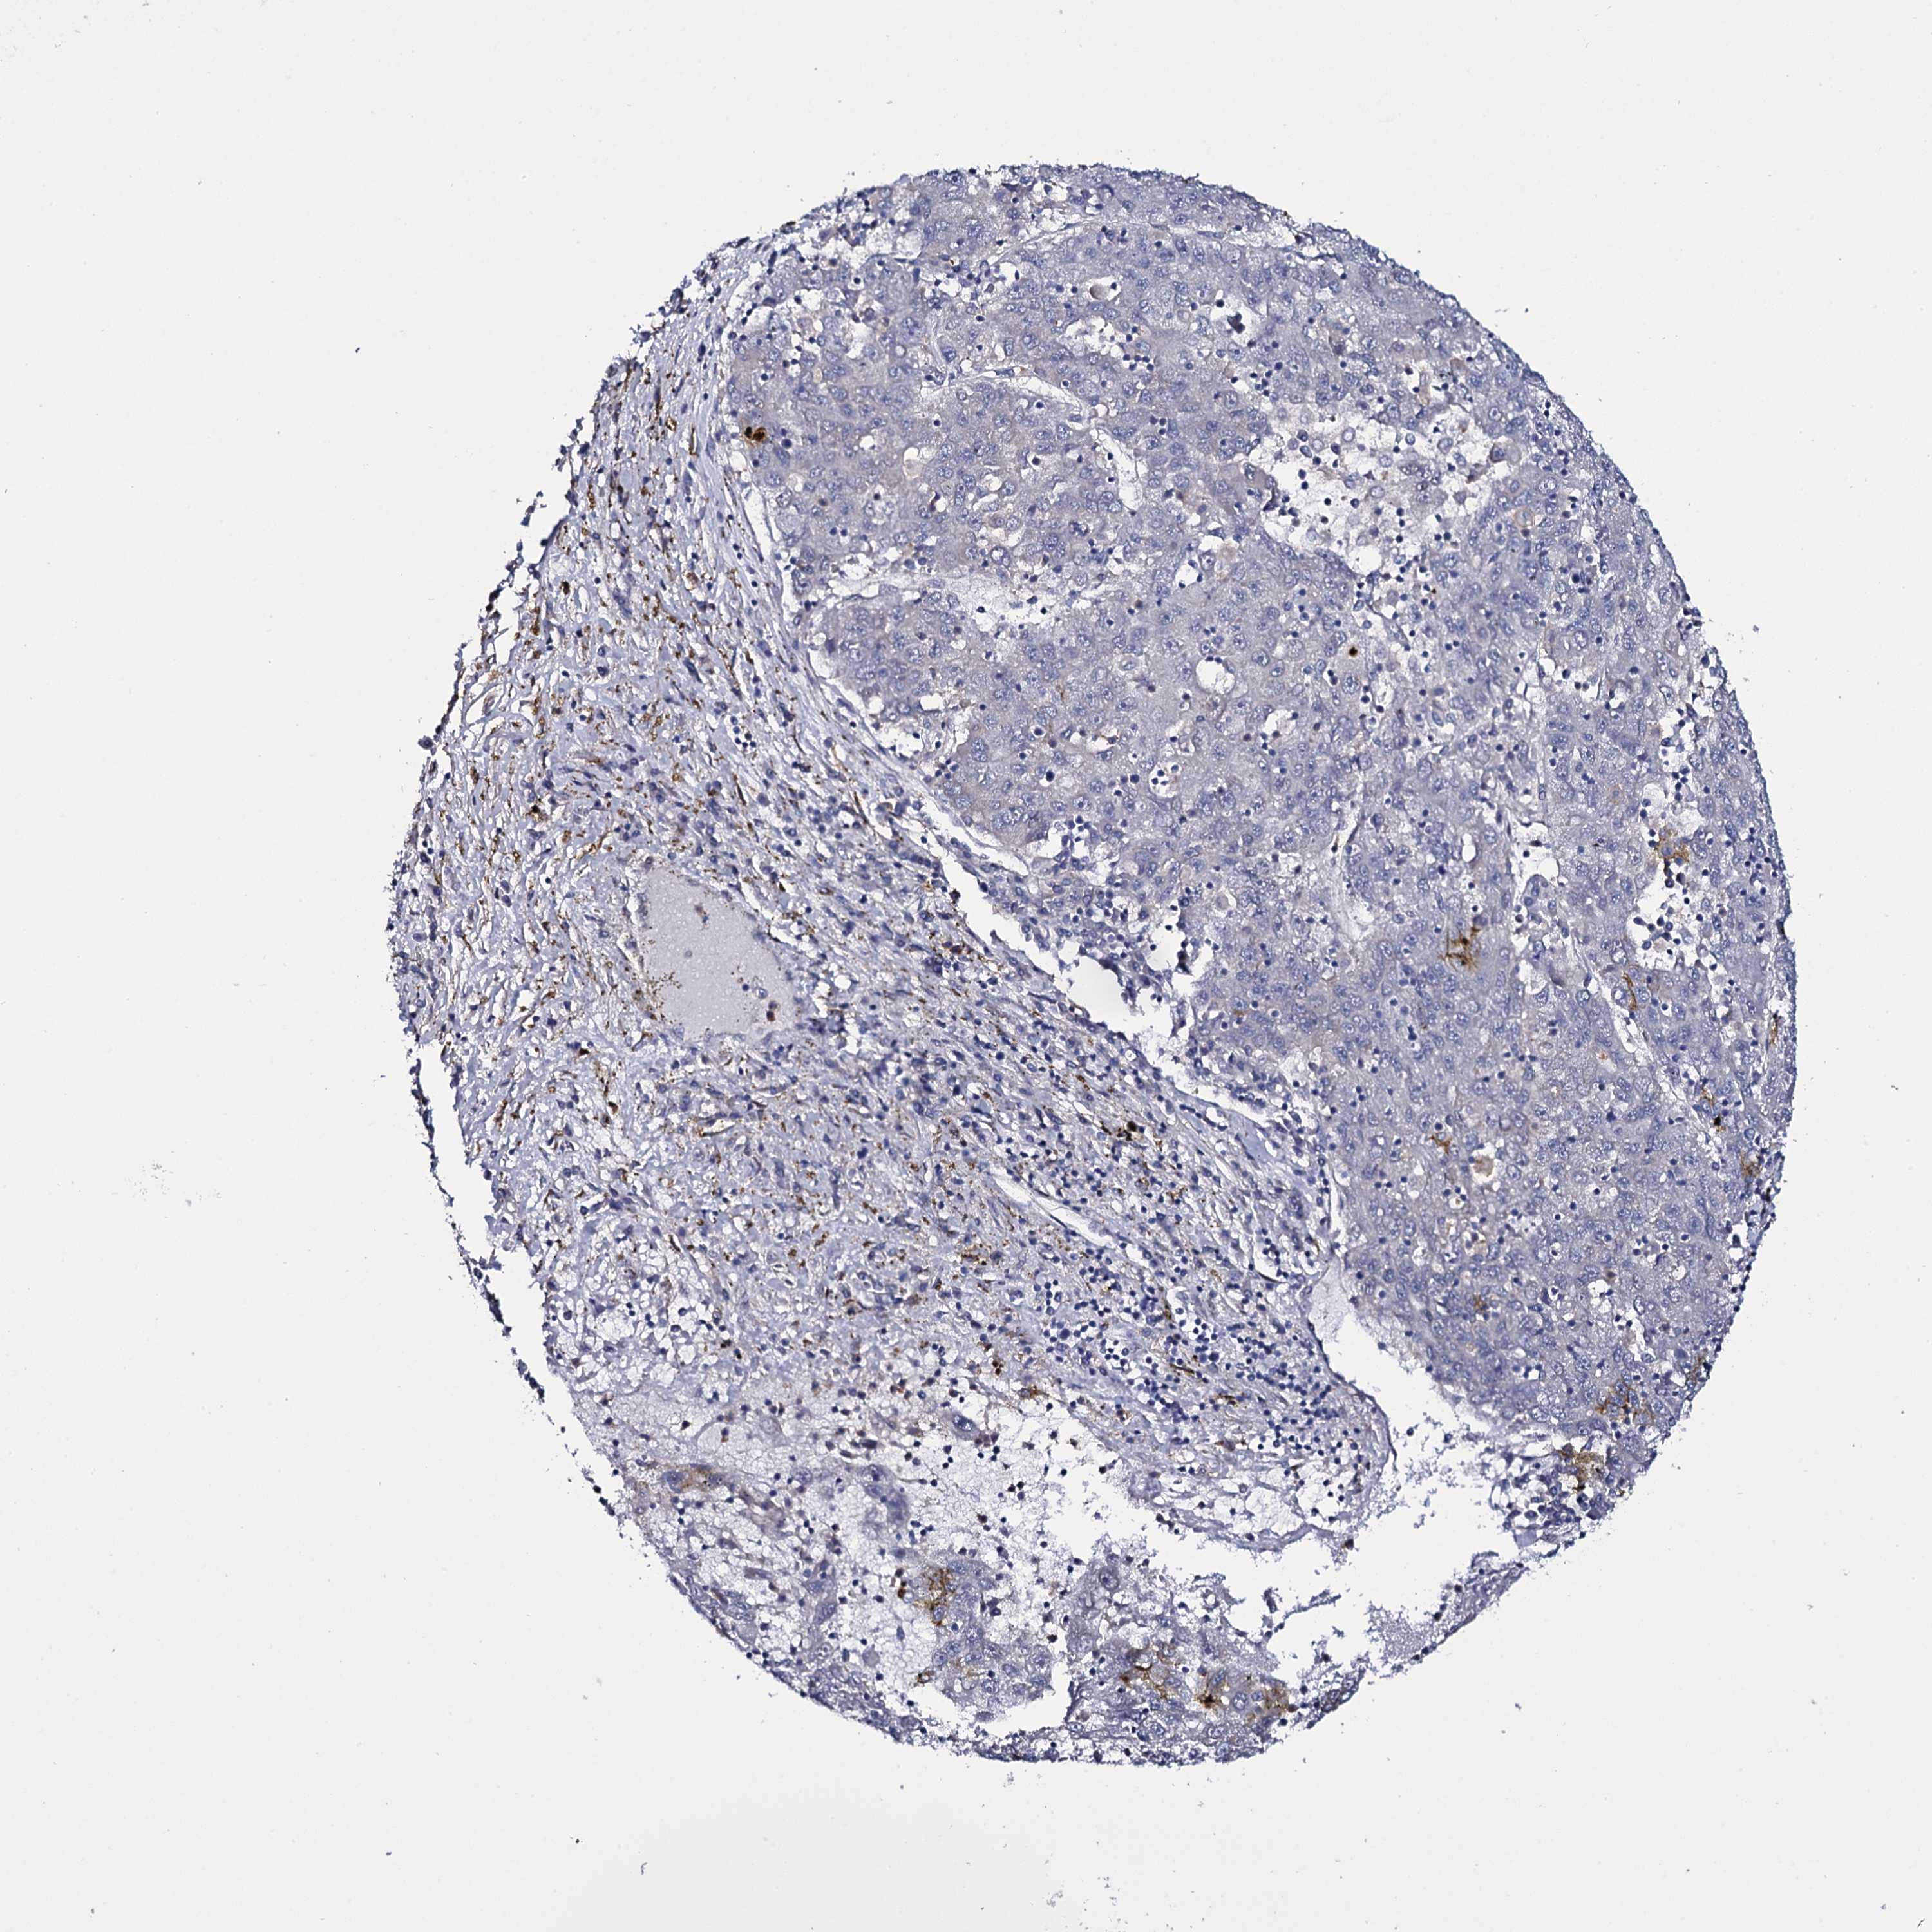

LIVER CANCER - Protein expressioni

A mouse-over function shows sample information and annotation data. Click on an image to view it in a full screen mode. Samples can be filtered based on level of antibody staining by selecting one or several of the following categories: high, medium, low and not detected. The assay and annotation is described here.

Note that samples used for immunohistochemistry by the Human Protein Atlas do not correspond to samples in the TCGA dataset.

Antibody stainingi

Antibody staining in the annotated cell types in the current human tissue is reported as not detected, low, medium, or high, based on conventional immunohistochemistry profiling in selected tissues. This score is based on the combination of the staining intensity and fraction of stained cells.

Each image is clickable and will lead to virtual microscopy that enables deeper exploration of all samples and also displays staining intensity scores, fraction scores and subcellular localization as well as patient and tissue information for each sample.

Antibody HPA039806

Antibody HPA040369

Staining

High

Medium

Low

Not detected

Intensity

Strong

Moderate

Weak

Negative

Quantity

>75%

75%-25%

<25%

None

Location

Nuclear

Cytoplasmic/membranous

Cytoplasmic/membranous,nuclear

Cholangiocarcinoma

Carcinoma, Hepatocellular, NOS